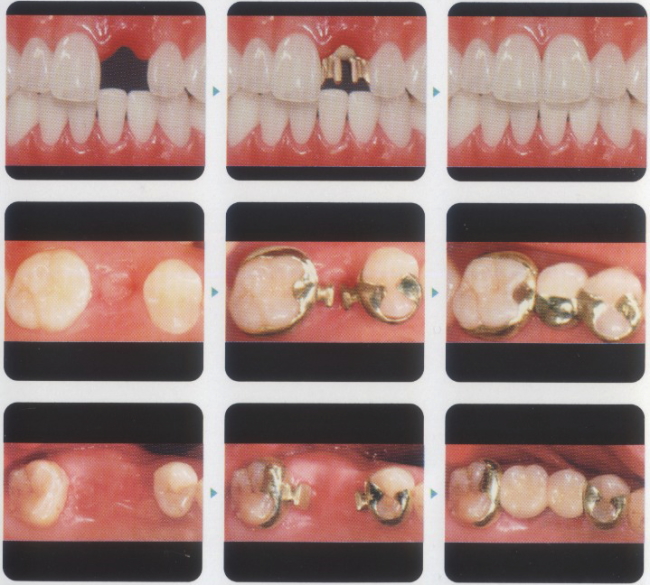

症例①

担当技工所の営業さんによると富山県内初となった症例を紹介します。自らの撮影により照明にムラがありますがご了承ください。20代女性、咬み合わせの不良により右下小臼歯(4番)1本を失ってしまいました。

●抜歯後の様子

●隣の小臼歯(5番)に詰め物(保険)をしていたので一旦取り外しました。

●手前の前歯(3番)には裏側にわずかな溝を入れました。どこか解らないほどのわずかな溝です。精密な型取りをしたのち、パーツが出来上がるまでの間に両隣の歯が倒れたりして動かないよう、人工歯付きのマウスピース(スプリントテック)を装着していただきました。

●約3週間後、完成したヒューマンブリッジのパーツを入れてみました。まず手前の前歯(3番)に装着。前からの見た目は何ら変わりません。

|

|

●そして小臼歯(5番)に装着。

|

|

●最後、真ん中の人工歯をはめこんで完成です。人工歯には白金加金にポーセレンを焼き付けてあります。この症例では、奥歯は金属の詰め物で治しましたが、それ以外は外から見ても金属のパーツが入っているようには見えません。ヒューマンブリッジは審美的にも優れた治療法です。

|

|